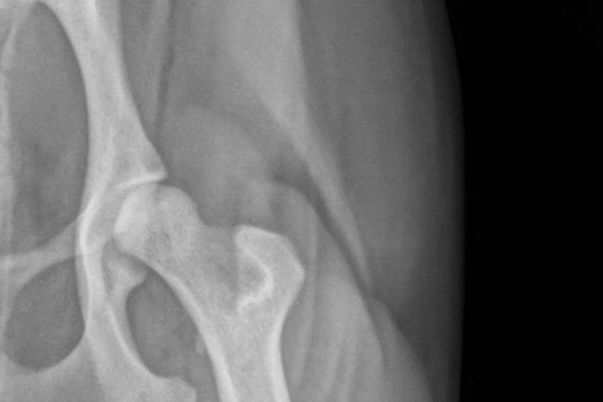

On his 2nd birthday, he began falling over nothing and the pain on his face was palpable. He knew it wasn't me and would run to me not using one leg. A few days ago he couldn't make it up one step and fell off, he screamed and I immediately made an appointment with the 3rd vet. I was grateful that this wonderful vet was more inquisitive. She immediately found two problems. The first one being the most important part and why the funding. She told me his knee cap was not staying in place even for a second. Normally when dogs have knee issues they can help train the knee cap to stay in place better. But not Kupo... His is off to the inside and up into his upper thigh as shown below.

In other x-rays she showed tendon damage. The other thing they were concerned with was his hip. When they saw his left hip, they were concerned that even if he had surgery that his right hip wouldn't be able to support his weight because his left hip has too small of a ball and was sliding.

They said that since he was so young, they would advise surgery but it would be expensive. His right hip ball join is a little larger but still lacking but would be okay to support him through the recovery process.